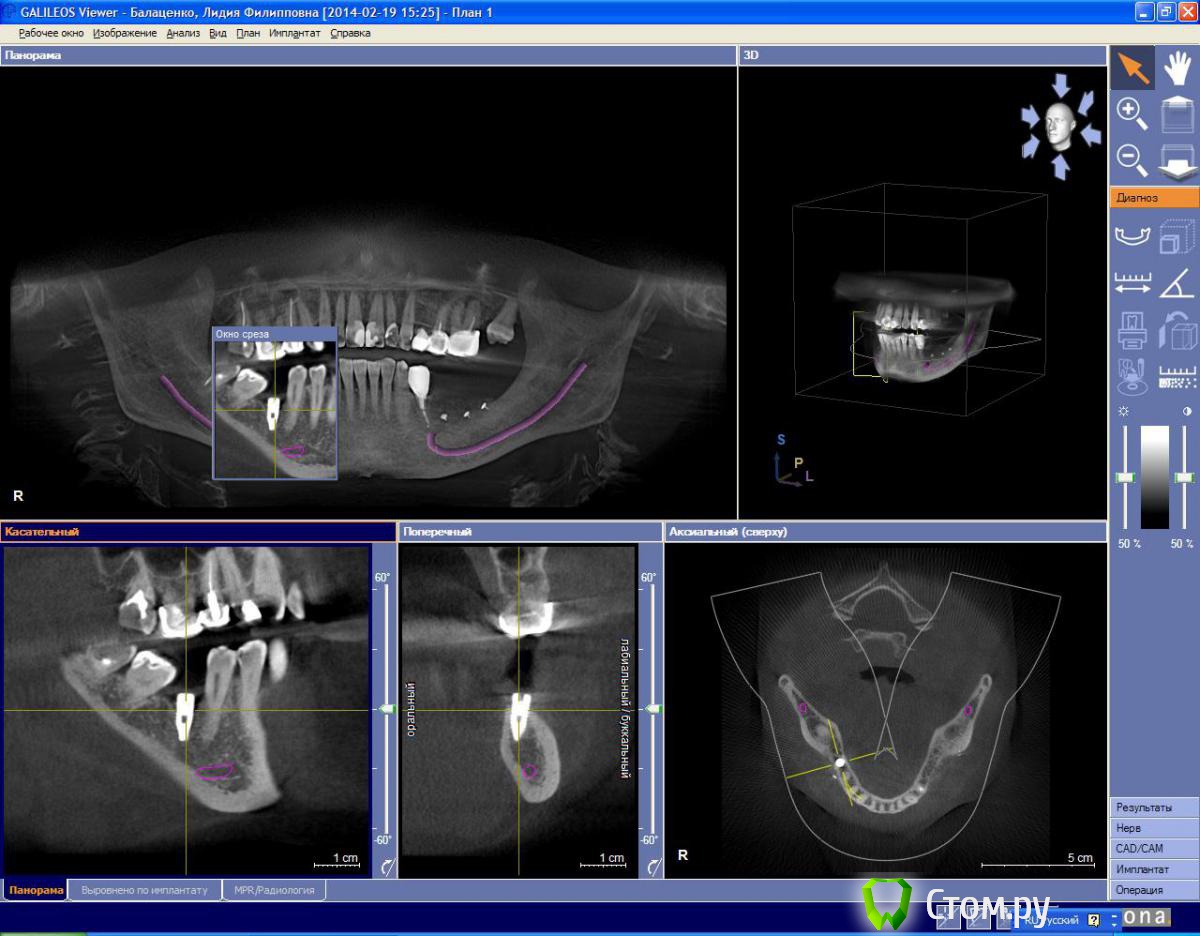

Владмир Опубликовано 6 марта, 2014 Поделиться Опубликовано 6 марта, 2014 Спасибо по поводу слизистой так и сделано прикрыл сст!!!! имплантат устанавливался вровень с язычной стенкой присыпалось только с вестибулярной стороны!!! Надо поискать кт до импл!!!Если наклонять язычно то протезировать проблематично же будет вроде!!)))У ортопедов в гос поликлинике другой план, депульпировать 47 и вывести вкладкой ))))так он у вас на щечный бугор в/ч направлен а должен на язычный если по срезу смотреть Ссылка на комментарий

Libero15 Опубликовано 7 марта, 2014 Поделиться Опубликовано 7 марта, 2014 По второму кейсу: мне показалось что это грануляции, мягкие ткани и т.п., может просто показалось?) Ссылка на комментарий

zzkz Опубликовано 7 марта, 2014 Поделиться Опубликовано 7 марта, 2014 По второму кейсу: мне показалось что это грануляции, мягкие ткани и т.п., может просто показалось?)мне тоже так показалось Ссылка на комментарий

StomDoc Опубликовано 7 марта, 2014 Автор Поделиться Опубликовано 7 марта, 2014 По второму кейсу: мне показалось что это грануляции, мягкие ткани и т.п., может просто показалось?)Нет это имплантат при установке надломил тонкую кость при препарировании!!! Ссылка на комментарий

StomDoc Опубликовано 7 марта, 2014 Автор Поделиться Опубликовано 7 марта, 2014 так он у вас на щечный бугор в/ч направлен а должен на язычный если по срезу смотретьДа, можно было наклонить немного почему то ориетировался вроде по соседним зубам так и получилось!!!!как во время формирования ложе соориентировать сверло на верхний бугор без шаблона??? Или только шаблон?? Ссылка на комментарий